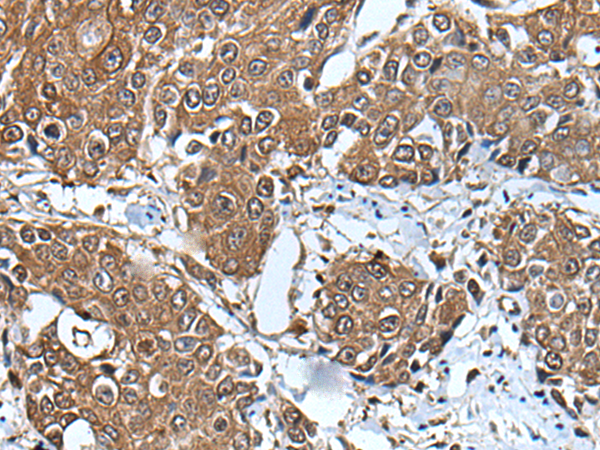

IHC positive control: |

Human colorectal cancer and human tonsil |